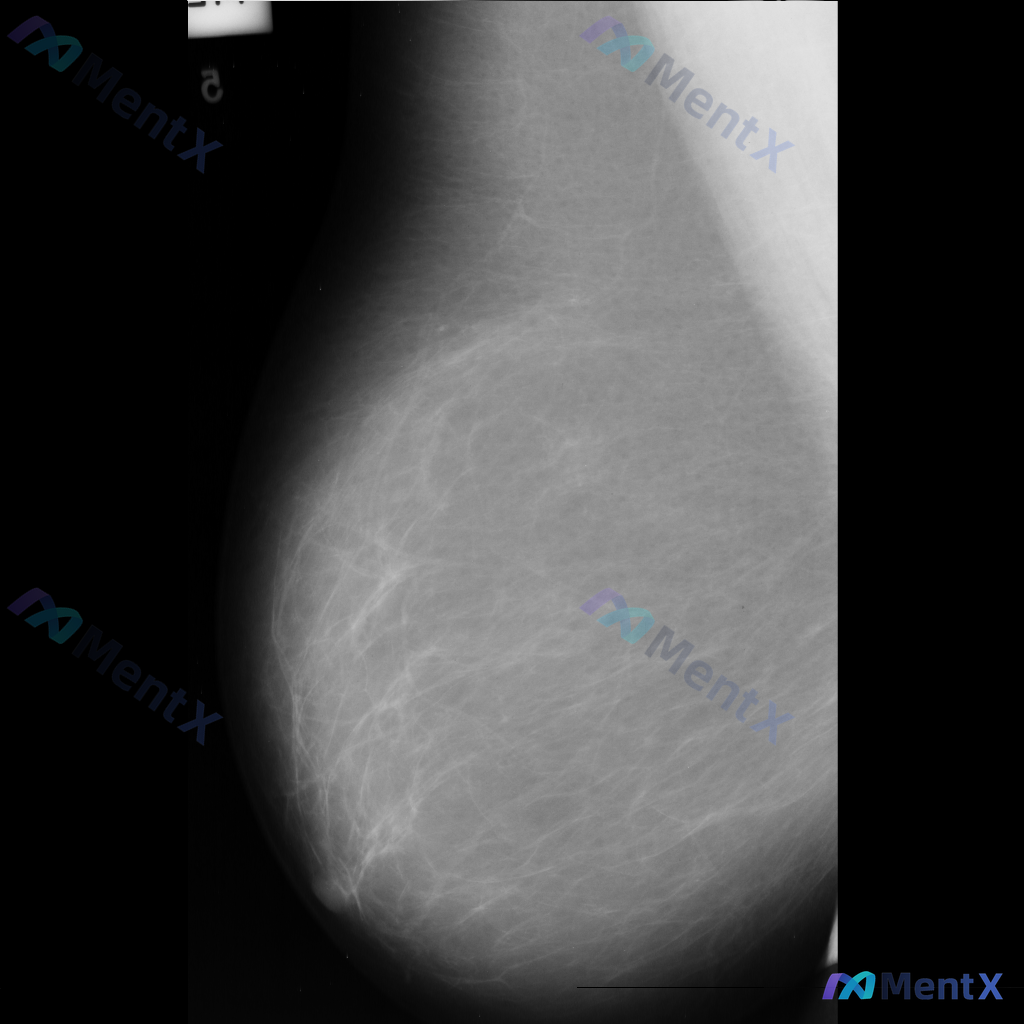

整理到一份单张的乳腺钼靶影像资料,仅有单侧、单幅图像,没有对侧对照,也不确定是MLO位还是CC位。

目前能看到的信息大概是:

- 乳腺类型看起来是多量腺体型

- 图像上没有看到明确的肿块、可疑的恶性钙化

- 皮肤、乳头、血管这些能看到的部分没有明显异常(不过图像范围没包含腋窝)